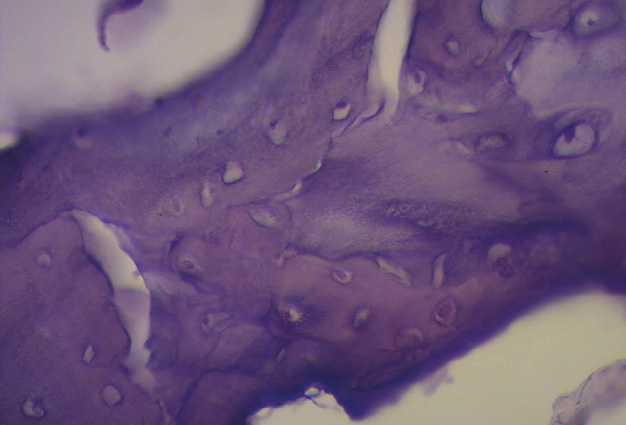

En bóvidos, la consistencia del fulcro cardíaco, óseo a la palpación (figuras 34 y 35), ha sido confirmada por la histología (figuras 36 a 38). Su tamaño, corroborado por disección (figura 39) y tomografía computada (figuras 58 y 59), es de aproximadamente 37 a 45 × 15 mm y de forma triangular. El análisis microscópico del fulcro cardíaco bovino muestra una matriz osteocondral trabecular con líneas segmentarias. Su estructura general asemeja al crecimiento metafisario de los huesos largos. A mayor aumento se pueden observar trabéculas óseas con osteoblastos y líneas segmentarias secundarias a aposición ósea. Los mismos hallazgos histológicos se han encontrado en chimpancés (109). La inserción secuencial de las fibras miocárdicas en el fulcro bovino se puede observar en las figuras 40-42.

Figura 34. Fulcro cardíaco en corazón bovino. En el ángulo derecho se observa la imagen microscópica de la inserción del miocardio en la matriz ósea.

Figura 36. Técnica de hematoxilina y eosina. En el campo se observa tejido óseo trabecular con líneas de segmentación osteológica correspondiente al fulcro cardíaco (corazón bovino). Técnica de hematoxilina-eosina (40x).

Figura 37. Técnica de hematoxilina-eosina (10x). Trabécula ósea madura que configura el tejido del fulcro cardíaco (corazón bovino).

Figura 38. Tinción con hematoxilina-eosina a gran aumento (40x) del fulcro cardíaco. Se observa una trabécula ósea con osteoblastos y líneas segmentarias. La estructura forma el andamiaje del tejido óseo trabecular similar a las zonas metafisiarias de crecimiento de los huesos largos. Se visualizan trabéculas óseas con osteoblastos y líneas segmentarias secundarias a aposición ósea (corazón bovino).

Figura 40. Inserción del miocardio en el fulcro cardíaco (corazón bovino). Técnica de hematoxilina-eosina (15x).

Figura 41. Se observa la inserción de fibras miocárdicas en el tejido condroide (fulcro) en corazón de bóvido. Técnica de hematoxilina-eosina (40x).

Figura 42. En corazón de bóvido se observa, en medio del fulcro, miocardiocitos del segmento derecho. Técnica de hematoxilina-eosina (40x).